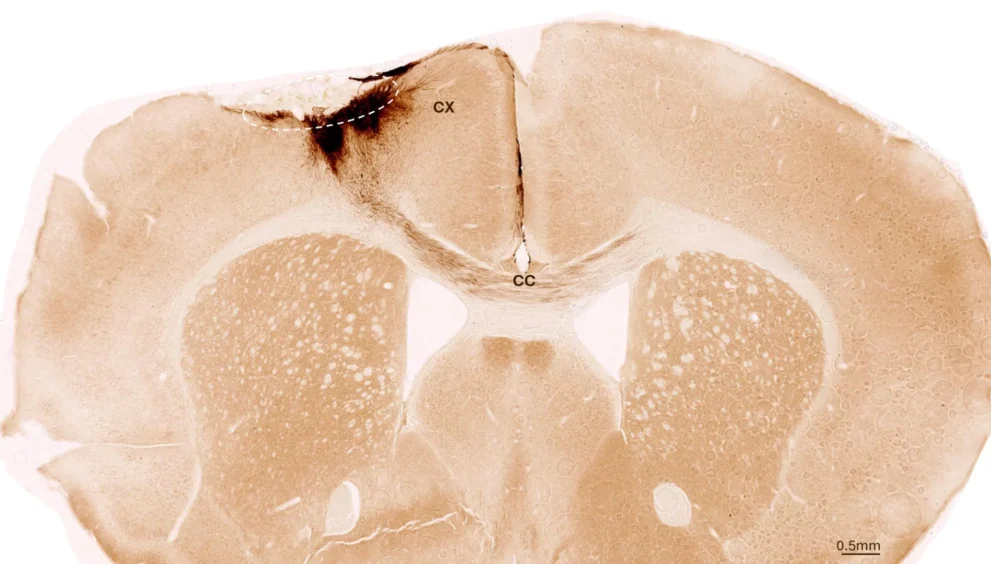

Uma semana após a indução do AVC, a equipe de pesquisa transplantou células-tronco neurais na região cerebral lesionada e observou os desenvolvimentos subsequentes usando uma variedade de métodos de imagem e bioquímicos. “Descobrimos que as células-tronco sobreviveram durante todo o período de análise de cinco semanas e que a maioria delas se transformou em neurônios, que na verdade até se comunicavam com as células cerebrais já existentes”, afirma Tackenberg.

Os pesquisadores também identificaram outros marcadores de regeneração: nova formação de vasos sanguíneos, atenuação dos processos de resposta inflamatória e melhoria na integridade da barreira hematoencefálica. “Nossa análise vai muito além do escopo de outros estudos, que se concentraram nos efeitos imediatos logo após o transplante”, explica Tackenberg. Felizmente, o transplante de células-tronco em camundongos também reverteu as deficiências motoras causadas pelo AVC. A prova disso foi fornecida em parte por uma análise da marcha dos camundongos assistida por IA.